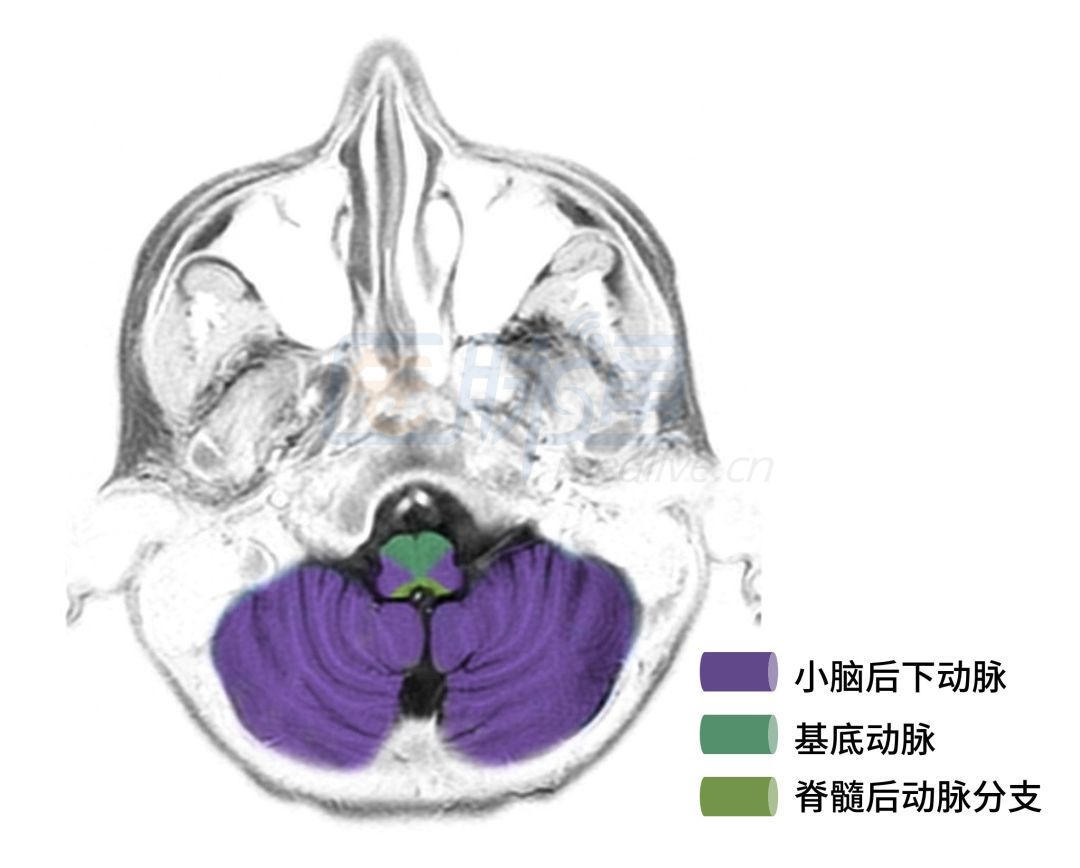

图3 延髓下部层面

图4 延髓层面

图3、4显示的层面主要是延髓和小脑血管供应区域。

❖ 脊髓前动脉:供应脊髓前2/3,闭塞可引起病灶水平以下上运动神经元瘫痪、分离性感觉障碍和膀胱直肠功能障碍。

❖ 脊髓后动脉:供应脊髓后1/3,闭塞可引起病灶水平以下深感觉障碍。

❖ 基底动脉:后部分支供应延髓内侧,闭塞可引起同侧舌肌麻痹和萎缩,对侧上下肢中枢性瘫痪以及触觉、位置觉、振动觉减退或丧失,即Dejerine综合征。

❖ 小脑后下动脉:供应延髓,闭塞可引起延髓背外侧综合症;供应小脑半球的下面以及扁桃体,闭塞可引起同侧肢体共济失调。